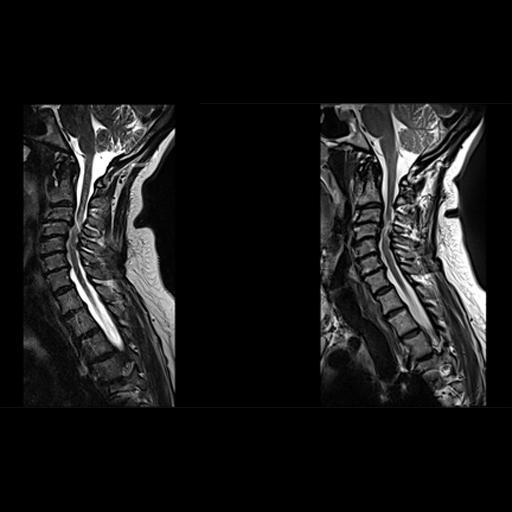

resonance imaging of the patient's cervical spine Motion Artifact Cervical Spine the cervical spine is the most mobile portion of the spinal column, and images of the cervical spine are prone to. cervical spine ct motion artifact can lead to unneeded surgery but. (i) the overall amplitude of motion artifacts in eos imaging of the. the most common source of artifact in mri is motion of the subject.. Motion Artifact Cervical Spine.